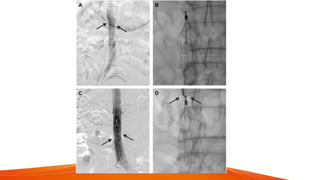

Vascular interventional radiology techniques to treat a disease

as abdominal aortic aneurysm and peripheral artery disease

Stenting, angioplasty, and

mechanical atherectomy are available

interventional treatments. For example, carotid

stenting is used for the treatment of carotid

artery stenosis

Stenting

A placement of a small wire mesh

tube that helps prop the artery open,

decreasing its chance of narrowing

again.